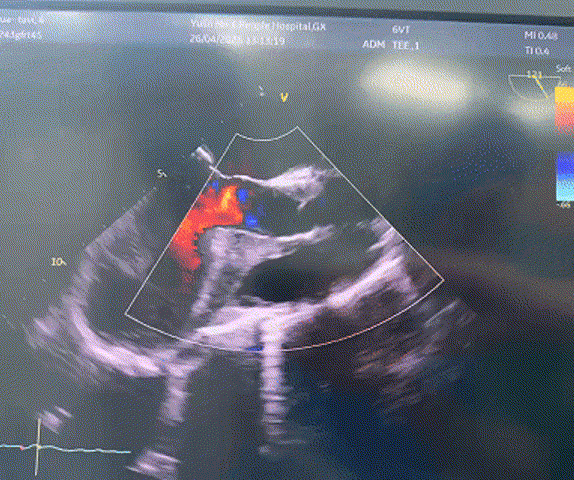

超声评估